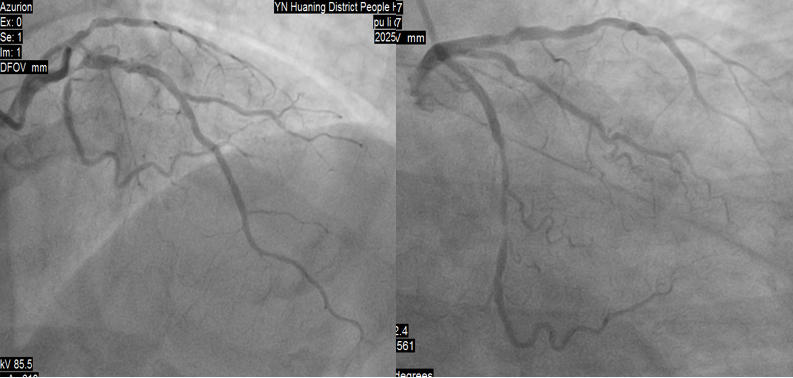

虽然患者胸痛明显缓解,考虑到梗死面积大,于11:20送达导管室,冠脉造影示:均势型,右冠全程弥漫性病变,最狭窄处50%,中段囊性扩张,血流3级;左主干未见明显异常;前降支近段次全闭塞,血流3级;回旋支中段次全闭塞,血流3级。

造影显示溶栓再通,12:20完成前降支、回旋支PCI手术。